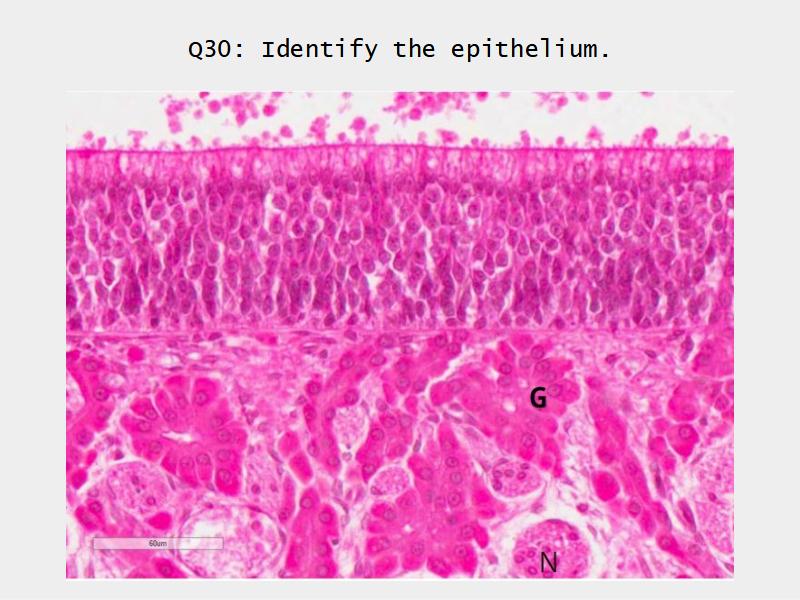

Respiratory epithelium

- Pseudostratified

- Ciliated

- Columnar

- Epithelium with

- 4 Cells

- Ciliated columnar cells

- Non-ciliated columnar cells

- Goblet cells

- Basal cells

Trachea

Clara cells

Read more about the use of eponyms.